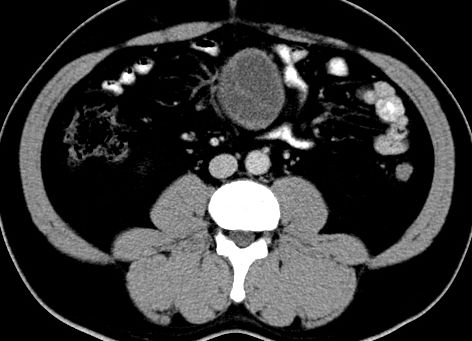

(腹腔)神经鞘瘤

男,48岁,间断性下腹不适1年。

手术探查

:距回盲部28厘米处肠系膜根部可见5*7cm左右包块,质中等硬度,活动度尚可,肝、胆、胰、脾肾未见明显异常。

病理

:(腹腔)

神经鞘瘤

,伴出血、坏死及囊性变,伴淋巴结反应性增生。

免疫组化结果

:sma(-), desmin(-), cd117(-), s-100(+++), nf(-),vimentin(+++).